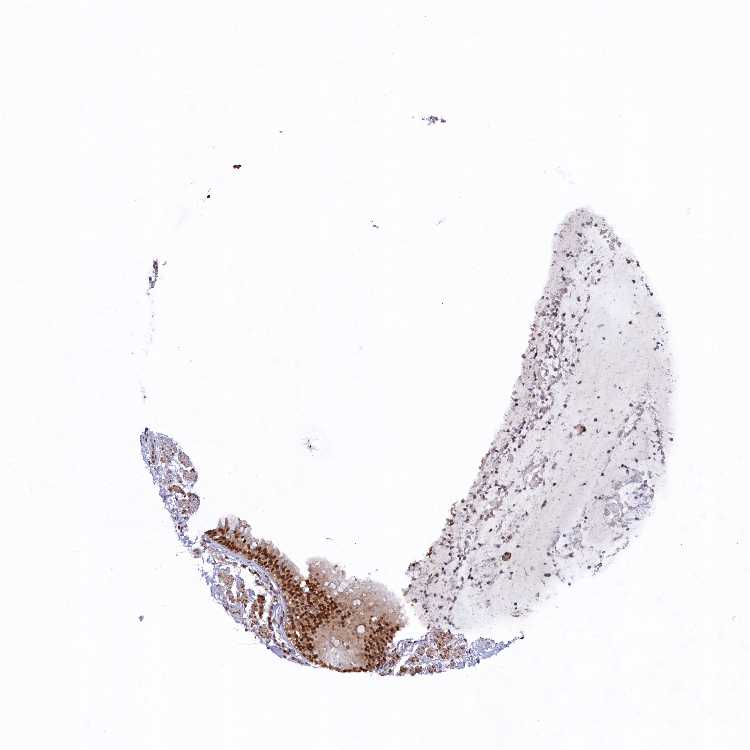

ADIPOSE TISSUE - Antibody stainingi

Antibody staining in the annotated cell types in the current human tissue is reported as not detected, low, medium, or high, based on conventional immunohistochemistry profiling in selected tissues. This score is based on the combination of the staining intensity and fraction of stained cells.

Each image is clickable and will lead to virtual microscopy that enables deeper exploration of all samples and also displays staining intensity scores, fraction scores and subcellular localization as well as patient and tissue information for each sample.

Antibody HPA041225Antibody HPA044675

Adipocytes Not detectedNot detected